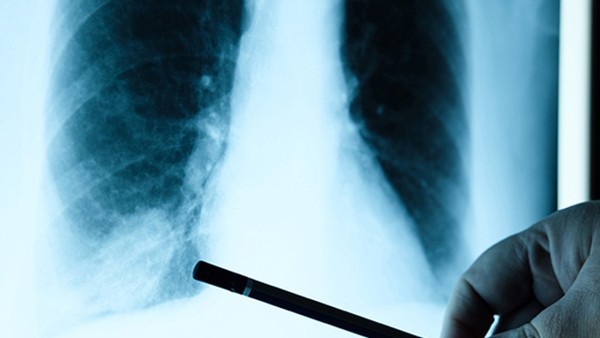

社区获得性细菌性肺炎常见的临床表现

社区获得性细菌性肺炎是一种在社区环境中感染的肺部疾病,通常由细菌引起。这种疾病常见于各个年龄段的人群,尤其是年长者、免疫系统功能受损者以及患有慢性疾病的人。其症状可以各不相同,但一些常见的临床表现有助于早期诊断和治疗。 1. 呼吸症状:患者常表现为呼吸急促、咳嗽和咳痰。咳嗽可能伴有痰液,通常是黄绿色的,有时可能带有血丝。严重感染时,呼吸困难可能变得明显。 2. 发热:发热是社区获得性细菌性肺炎最常见的症状之一。患者体温通常超过正常体温(37.8摄氏度或98.6华氏度),发热可能伴有寒战和全身不适。 3. 胸痛:部分患者可能出现胸部不适或疼痛,疼痛可能是持续的或间歇性的,加重于呼吸或咳嗽时。 4. 乏力和虚弱感:患者可能感到整体乏力、疲倦和虚弱,这种感觉可能与持续的发热和呼吸困难有关。 5. 嗜睡或混乱:在一些情况下,特别是年长者或有基础疾病的患者,可能表现出嗜睡、精神状态改变或混乱的症状。 6. 恶心、呕吐和腹泻:虽然较少见,但某些细菌性肺炎患者也可能出现消化道症状,如恶心、呕吐和腹泻。 7. 其他症状:在某些情况下,患者还可能出现心悸、头痛、皮肤发紫等症状,具体表现因人而异。 总的来说,社区获得性细菌性肺炎的临床表现多种多样,具体症状受患者年龄、健康状况、病因、感染严重程度等因素影响。早期诊断对于及时采取治疗至关重要。如果您或您身边的人出现上述症状,特别是伴随呼吸困难等严重症状时,应尽快就医,以获取专业的诊断和治疗。在治疗过程中,请严格遵循医生的建议,完成整个抗生素疗程以确保病情得到有效控制和治愈。